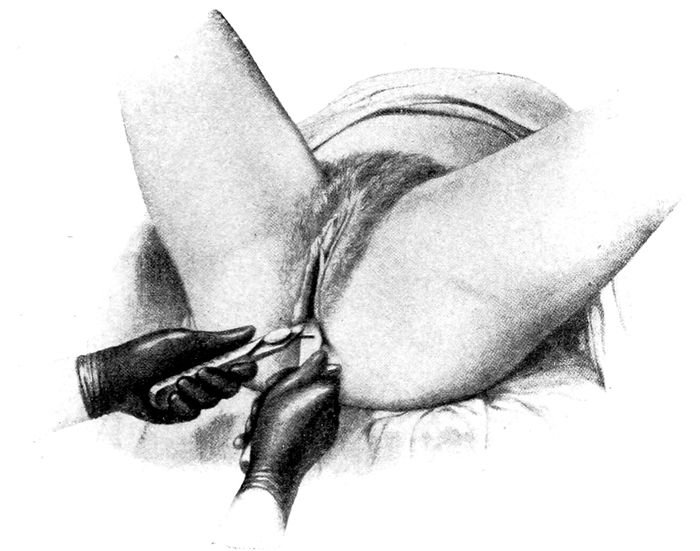

190 |

| 81. |

191 |